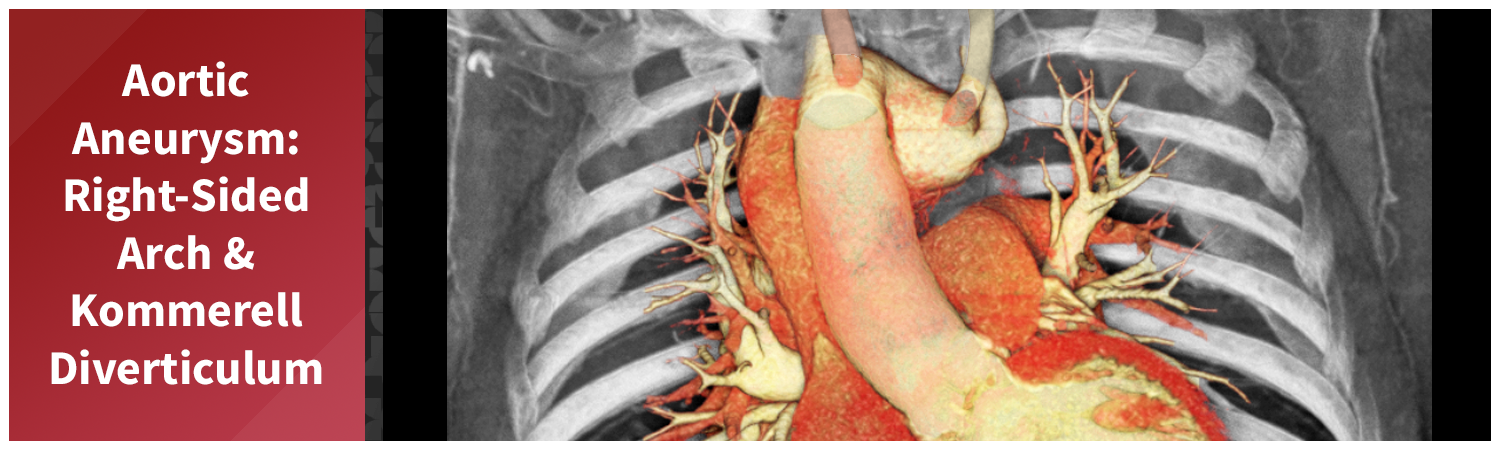

This case, however, involved unusual anatomy. The patient had a right-sided aortic arch, a congenital anomaly in which the aorta curves to the right side of the chest instead of the left. The branching pattern was also atypical. The first branch from this patient’s arch was the left common carotid artery, followed by the right common carotid and right subclavian arteries. The final branch was an aberrant left subclavian artery, which arose from a large Kommerell diverticulum, an outpouching often associated with arch anomalies. The descending thoracic aorta was tortuous, with an aneurysm identified at its proximal portion.

Figure A (Right): 4D rotational volume render of the heart and thoracic aorta, showing the arch branching pattern, Kommerell diverticulum, and proximal descending aneurysm. (Learn more about 4D/ time resolved imaging here).

A gated CT angiography of the chest was obtained to generate the images and measurements needed for aortic surveillance. This scan was the most recent in a series of follow-up studies since the patient was first identified with an aortic aneurysm and arch anomalies. The aortic surveillance program relies on these regularly scheduled scans to track changes over time. Measuring data over time is part of a process known as longitudinal analysis, learn more here. In this case, the Kommerell diverticulum has maintained a mostly consistent size over time, while the proximal aortic aneurysm has shown measurable enlargement.